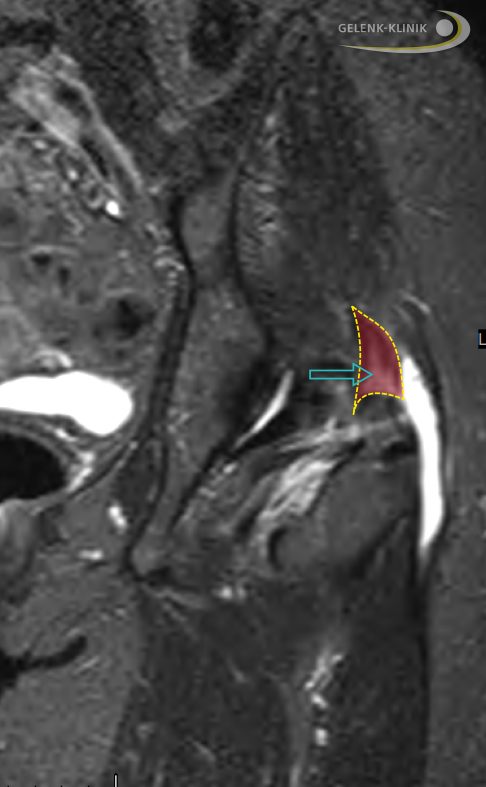

Schleimbeutelentzündung am Hüftgelenk

Im Hüftgelenk finden sich eine Vielzahl von Schleimbeuteln. Am häufigsten tritt die Schleimbeutelentzündung im Bereich des großen Rollhügels (Trochanter major) auf. Man spricht dann von einer Bursitis trochanterica. Das Laufen, Gehen und Springen beansprucht den Schleimbeutel in diesem Bereich extrem. Betroffene leiden unter Bewegungseinschränkungen und starken Hüftschmerzen, die auch in Ruhe nicht nachlassen.